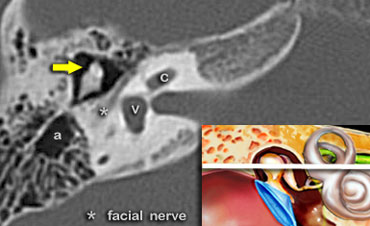

The head of the malleus is seen anterior to the head of the incus (yellow arrow).

Tympanic segment of the facial nerve

In this image at the level of the internal auditory canal, the tympanic segment of the facial nerve is seen just medial and parallel to the wall of the epitympanum.

The head of the malleus (yellow arrow) is seen anterior to the head and the short process of the incus.

Geniculate ganglion of the facial nerve

At this level the aditus ad antrum is seen. This is the connection between the tympanic cavity and the antrum.

The labyrinthine segment of the facial nerve coming from the internal auditory canal angles sharply forward, nearly at right angles to the long axis of the petrous bone, to reach the geniculate ganglion.

At the ganglion the facial nerve makes a U-turn (first genu of the facial nerve) to run posteriorly as the tympanic segment along the medial wall of the epitympanum.